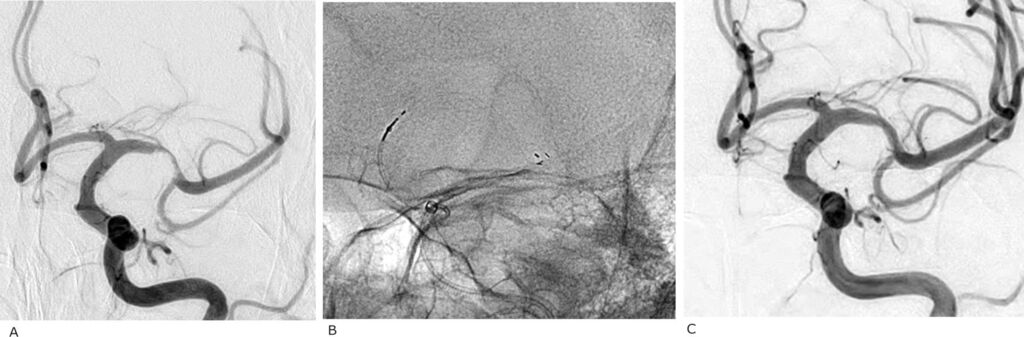

Early Flow-Diverter Implantation in Ruptured Intracranial Aneurysms: Safety and Outcomes in a Resource-Limited Setting neurointervention.org March 16, 2026, 9:56 a.m.

Early FD implantation in carefully selected ruptured aneurysms, including small saccular and morphologically complex lesions can achieve high functional recovery and complete angiographic occlusion, even in a resource-limited environment. Ideal case selection and standardized DAPT and hemodynamic protocols are critical. These findings support broader use in challenging aneurysms, but larger prospective studies are warranted to validate outcomes and refine management strategies.

Early Flow-Diverter Implantation in Ruptured Intracranial Aneurysms: Safety and Outcomes in a Resource-Limited Setting neurointervention.org March 11, 2026, 3:08 p.m.